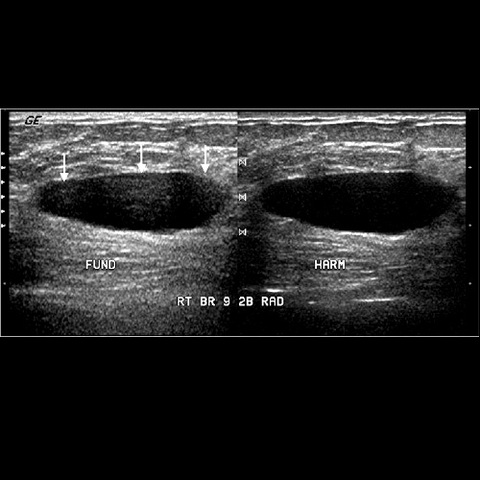

• More discoveries

More discoveries

Two major discoveries in digital technology directly influenced the field of ultrasound breast imaging.Those were tissue harmonics and spatial compounding. Tissue harmonics uses frequencies originating within the body, and spatial compunding uses multiple beams from different angles to create a better quality images. Referemce: